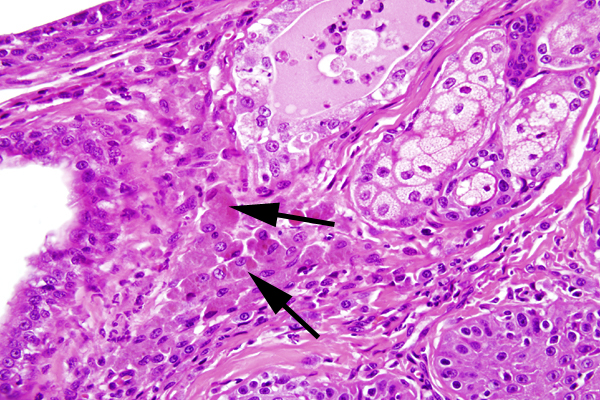

The stroma contains multifocal aggregates of many lymphocytes, fewer plasma cells, neutrophils and macrophages that are often laden with brown material (secretory product)(arrows).

The stroma contains multifocal aggregates of many lymphocytes, fewer plasma cells, neutrophils and macrophages that are often laden with brown material (secretory product)(arrows).